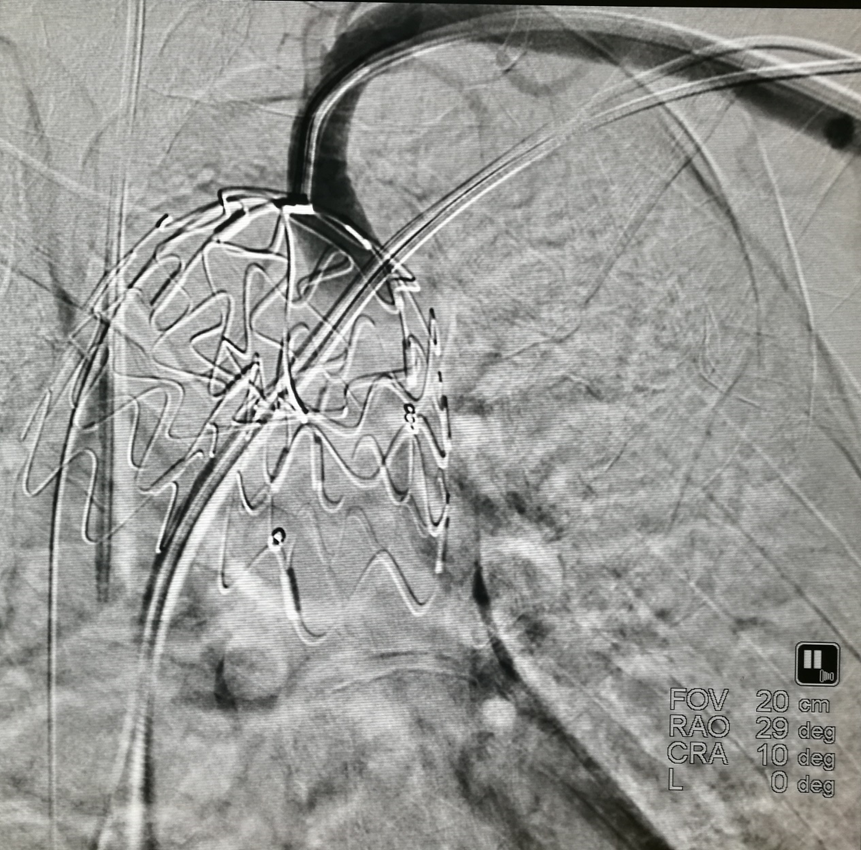

我们在两头35kg巴马公猪中完成动物实验:

成功实现弓上分支的快速、准确原位开窗;

破膜过程流畅,无分支或主动脉损伤;

取出标本可见圆形破口、支架贴合良好,证实技术可行性。

动物实验

巴马公猪35kg